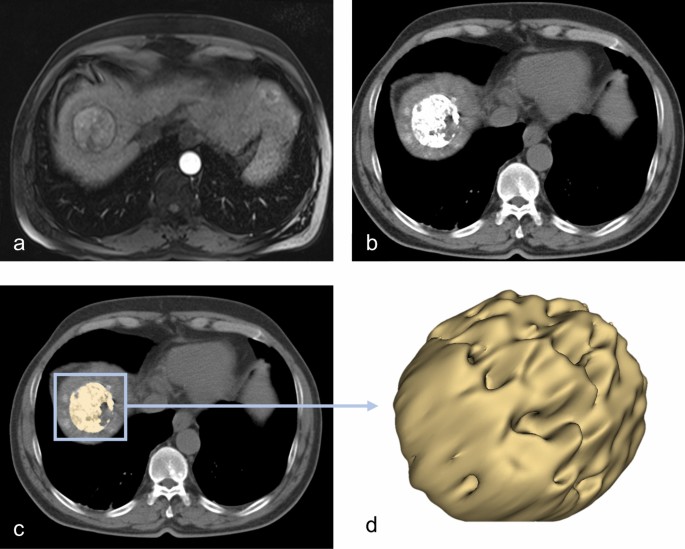

The image stack was visualized and processed using the 3D Slicer software platform (http://slicer.org, version 4.9.0)19,20. We resampled the images to a spacing of 1 mm × 1 mm × 1 mm prior to features extraction. One blinded investigator (OE, board-certified radiologist, 10 years of experience) tagged and segmented a maximum of two TLs per patient using the 24 h post-embolization CT after the first TACE. The tagged TLs were independently segmented by a second blinded investigator (SB, radiologist-in-training, 3.5 years of experience). Segmentation was performed as follows: a three-dimensional volume of interest (VOI) was manually drawn in the HCC-lesion, sparing equivocal border zones. The semi-automatic grow from seeds algorithm was used to augment the VOI to match the whole tumor habitat20,21,22. Clear foci of segmentation error were manually erased using the brush-erase tool. A representative segmentation is shown in Fig. 2.

Workflow of the image analysis. (a) Baseline arterial-phase MRI showing mildly enhancing hepatocellular carcinoma. The 24 h post-TACE CT (b) was used to semi-automatically segment the lipiodol retention-pattern in three dimensions (c–d).